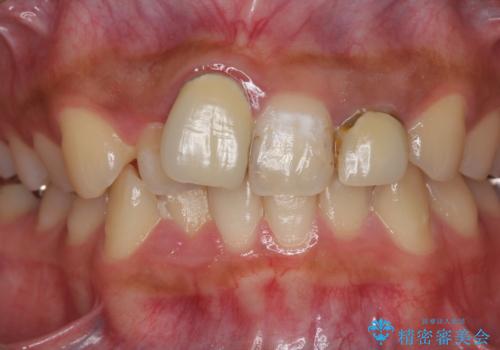

[ マウスピース矯正治療 ] がたつき ねじれのある前歯をきれいにしたい

![[ マウスピース矯正治療 ] がたつき ねじれのある前歯をきれいにしたいの症例 治療後](https://seimitsushinbi.jp/wp/wp-content/uploads/2025/04/IMG_0097-500x350.jpg?v=1745225947)